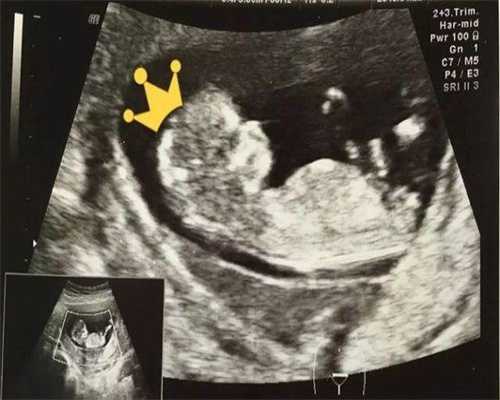

48岁高龄女性自然受孕的几率极低,但借助科学的辅助生殖技术,特别是供卵试管婴儿,可以有效应对生育挑战。供卵技术利用年轻健康的捐赠者卵子,极大地提高了胚胎质量和成功妊娠的机会,为实现助孕生子带来了希望。

- 规避高龄卵子染色体异常风险(48岁卵子异常率高达80%以上)

- 采用年轻卵子使胚胎着床率提升至30%-50%